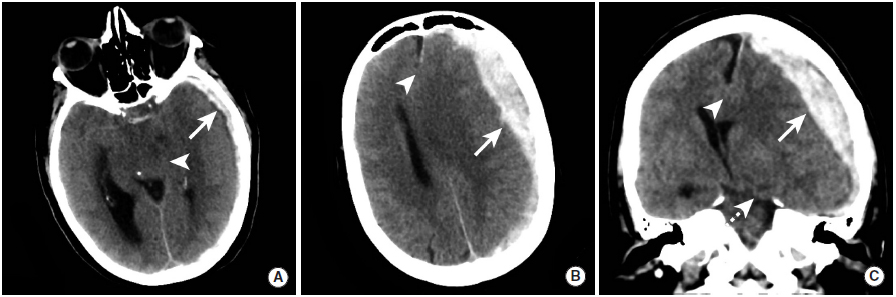

脑微出血

图6

本例患者接受了CT和MRI检查,以评估出血性实质性挫伤。与平扫CT(图A)相比,MRI的GRE(图B)和SWI(图C)序列显示的出血性挫伤(长尾箭头)更为显著。此外,GRE和SWI序列可见脑白质中的脑微出血(三角箭头)。

高血压引起的脑实质出血

图7

本例高血压性脑出血患者具有典型的“点状征”表现。

图A:CT平扫显示右侧基底节区大量脑出血(长尾箭头)。

图B:CTA扫描动脉期显示点状高密度影(长尾箭头),即“点状征”。根据“点状征”的定义,点状强化为血肿边缘与血管不相连的高密度灶。

图C:CTA扫描延迟期显示活动性出血灶中与图B相同位置的高密度影(长尾箭头)。

脑淀粉样血管病引起的脑实质出血

图8

本例患者的CT平扫(图A)、MRI的GRE(图B)和SWI(图C)序列显示右颞叶和枕叶的脑实质内出血(长尾箭头)。这种出血的典型表现是脑叶出血,并不限于动脉的供血区域。本例患者最终被诊断为脑淀粉样血管病。